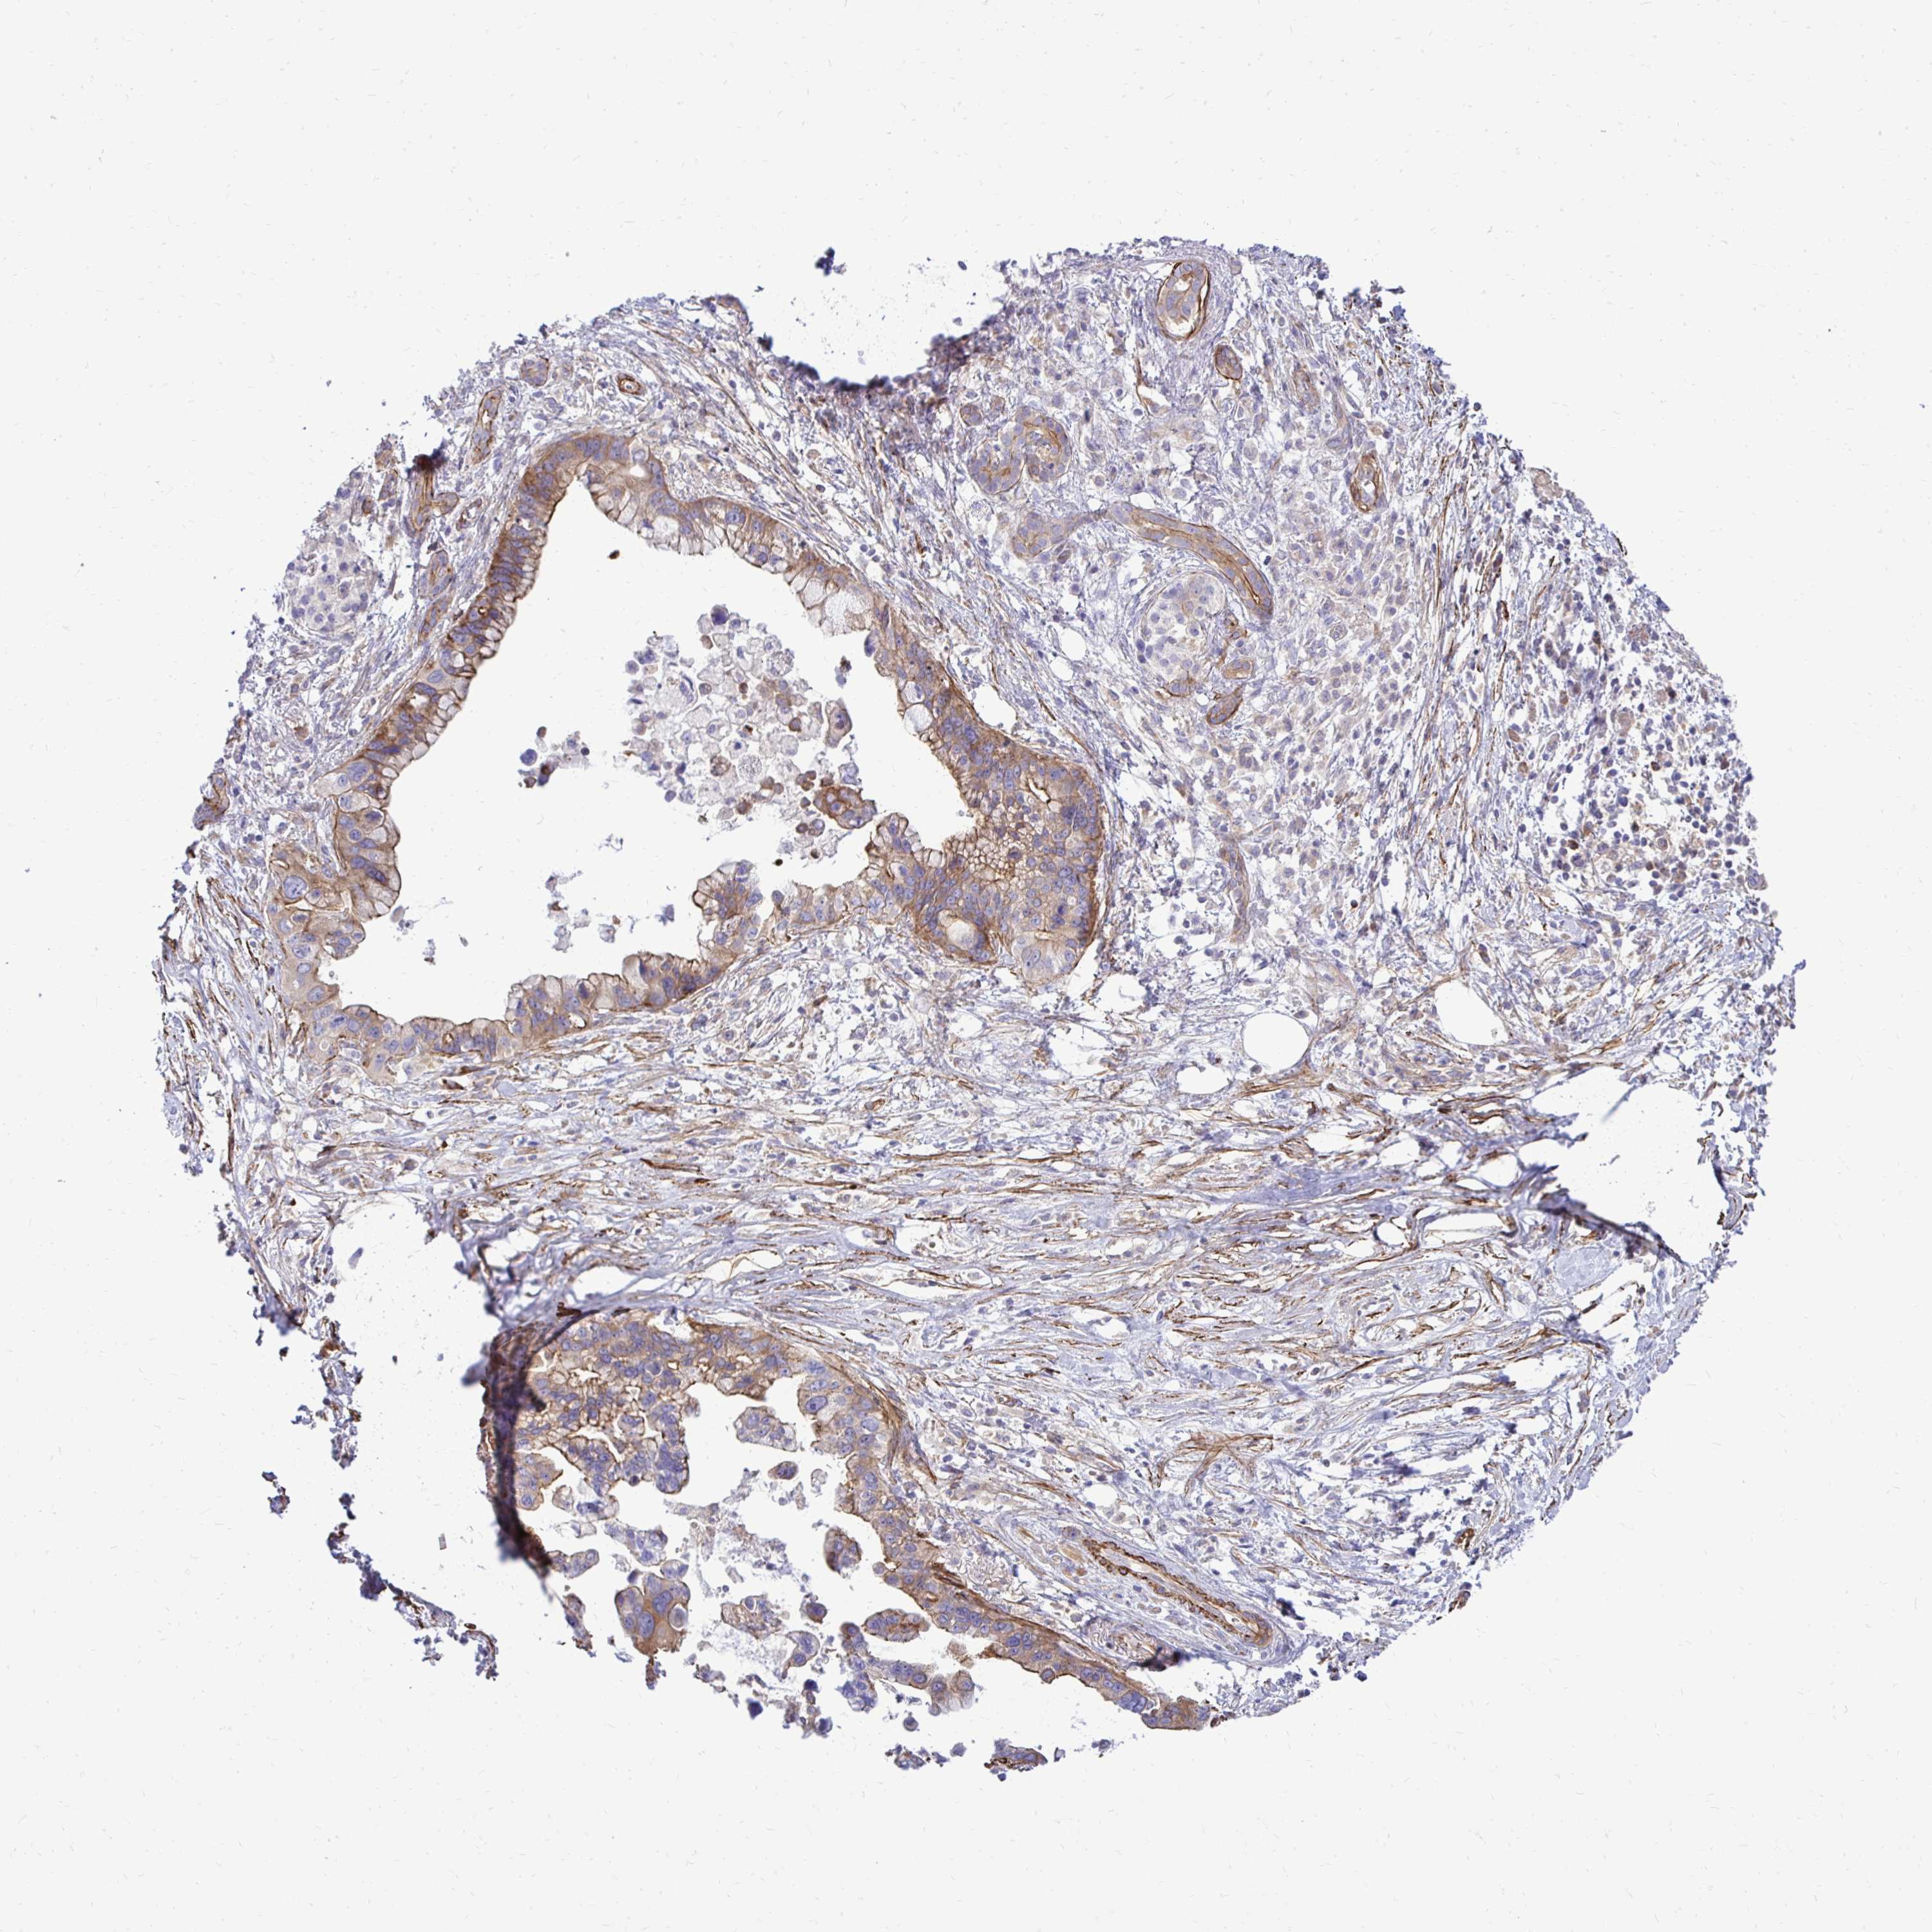

PANCREATIC CANCER - Protein expressioni

A mouse-over function shows sample information and annotation data. Click on an image to view it in a full screen mode. Samples can be filtered based on level of antibody staining by selecting one or several of the following categories: high, medium, low and not detected. The assay and annotation is described here.

Note that samples used for immunohistochemistry by the Human Protein Atlas do not correspond to samples in the TCGA dataset.

Antibody stainingi

Antibody staining in the annotated cell types in the current human tissue is reported as not detected, low, medium, or high, based on conventional immunohistochemistry profiling in selected tissues. This score is based on the combination of the staining intensity and fraction of stained cells.

Each image is clickable and will lead to virtual microscopy that enables deeper exploration of all samples and also displays staining intensity scores, fraction scores and subcellular localization as well as patient and tissue information for each sample.

Antibody HPA051322

Antibody CAB017111

Adenocarcinoma, NOS